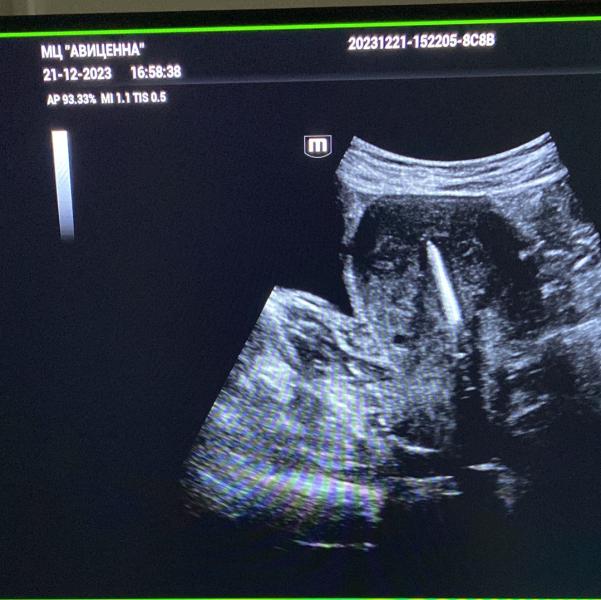

Установка спирали. Без боли и осложнений.

На 3 фото нежеланная беременность 8 недель.